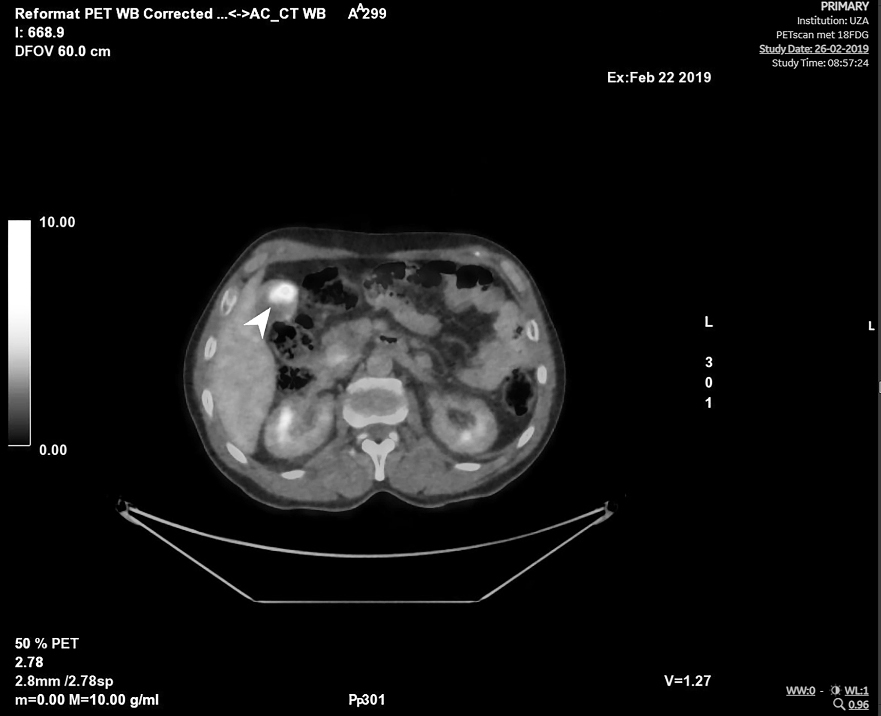

A 57-year-old man from Morocco was referred 109 days after initial presentation for bilateral progressive visual loss and concentric narrowing of visual fields over a period of more than 4 months. Visual loss occurred simultaneously in both eyes, although more severely in the right eye. He experienced photo-aversion and a glare around objects. No previous personal or familial history of ocular complaints was found. Systemic history at presentation: hypovitaminoses D, smoking, surgical inguinal hernia repair. At presentation, best corrected visual acuity (BCVA) using the Early Treatment of Diabetic Retinopathy Study chart (ETDRS-chart) was counting fingers for the right eye and 20/500 for the left eye. Clinical examination demonstrated bilaterally a mild anterior chamber reaction, vitreous opacities (more pronounced in the right eye) and a retinoschisis-like aspect inferiorly with a profound bullous separation of the inner and outer retinal layers. Intra-ocular pressure (IOP) was normal, measuring 10 mmHg in the right and 11 mmHg in the left eye with Goldmann applanation tonometry. Optical coherence tomography (OCT) showed an irregular ellipsoid zone in both eyes with mild loss of the foveal depression in the right eye (Figure 1 [Fig. 1]). Multiple hyperautofluorescent round lesions were visible on fundus autofluorescence (FAF) in the posterior pole (Figure 2 [Fig. 2]). A differential diagnosis of paraneoplastic or non-paraneoplastic autoimmune retinopathy and lymphoma was considered. Vitreal biopsy was considered for laboratory investigation, but due to practical circumstances this was not performed. A full-field electroretinogram (FF-ERG) was performed, which yielded an electronegative response in both eyes (Figure 3 [Fig. 3]), possibly indicating loss of bipolar cell function and photoreceptor function. Clinical findings combined with the electronegative electroretinogram (ERG) made us suspect CAR. Whole-body positron emission tomography-computed tomography (PET-CT) was ordered by the ophthalmologists team and showed accumulation of fluor-18-deoxyglucose (18F-FDG) at the gallbladder, lymphatic nodes near the liver hilus, axial bone(-marrow), pancreatic head, and peritoneally at the right paracolic gutter (Figure 4 [Fig. 4]). These findings suggested a metastasized gallbladder carcinoma, supporting the clinical suspicion of CAR. Cerebral magnetic resonance imaging (MRI) did not reveal any metastatic lesions. A liver endoscopic lymph node puncture biopsy was performed and immunohistochemistry rendered a small cell neuro-endocrine tumor (NET) most likely, with Ki67 40%. Lymphoma was excluded. Because of the CAR-symptoms, a trial of high-dose oral corticosteroids (methylprednisolone 1 mg/kg/day; stepwise dose reduction after 40 days of treatment) was started by the ophthalmological team in consensus with the oncologists. Due to practical arrangements, the multidisciplinary oncological team started palliative chemotherapy with carboplatin-etoposide 10 days after the initiation of oral high-dose corticosteroids. Combined chemo- and oral corticoid-therapy led to the gradual improvement of visual acuity. 18 days after initiation of oral corticoids and 8 days after initiation of chemotherapy the vitreal haze had resolved. At this point attenuated retinal arterioles could be detected. After 4 months of treatment the ETDRS-chart BCVA comprised 20/66 for the right eye and 20/20 for the left eye. Goldmann visual fields became recordable for V4 light stimuli and showed only mild bilateral concentric narrowing of the visual fields (Figure 5 [Fig. 5]). From the oncological point of view, additional immunosuppressive agents were only deemed safe after 4 months into follow-up. To this end, methotrexate was started at a dose of 6x2.50 mg/week, along with folic acid at this moment in time (azathioprine was initially started, but had to be discontinued because it was not supported by the patient). Additional indirect fluorescence in situ hybridization (FISH) showed an autoimmune reaction against retinal antigens in the inner nuclear, outer plexiform and photoreceptor layers (Figure 6 [Fig. 6]). This indicated the presence of anti-retinal autoantibodies and confirmed the diagnosis of CAR. Anti-recoverin antibodies were negative, determination of other different subtypes of anti-retinal antibodies was not performed. Unfortunately, the patient died 9 months after diagnosis secondary to complications of his primary tumor.

Figure 4: Positron emission tomography – computed tomography (PET-CT) shows gallbladder carcinoma, pathological lymphatic nodes near the liver hilus, and metastatic lesions in the pancreatic head and peritoneally at the right paracolic gutter.